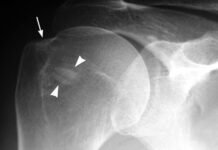

TENDINITIS CALCICA Que Es Y Como Tratarla

La tendinitis cálcica es la presencia de clasificaciones en los tendones. Los tendones que más afectados por la tendinitis cacica, son los del manguito...